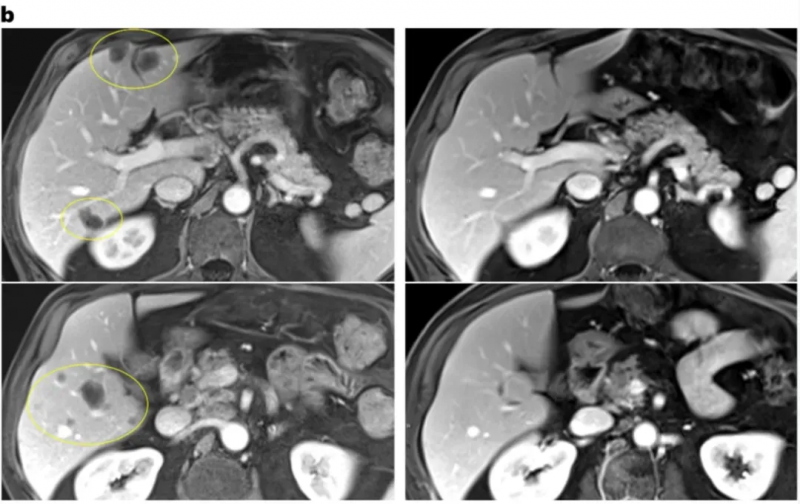

其中一位胆管癌患者,在治疗9个月时,骨骼及主动脉旁淋巴结两处肿瘤均消退,骨转移部位出现愈合迹象,肝脏、肺、肾上腺等其他病灶未在检查中呈现。

▲图源“Nat Med”,版权归原作者所有,如无意中侵犯了知识产权,请联系我们删除

另一位直肠癌患者,在治疗10个月时,肝脏两处肿瘤均缩小,肺部和淋巴结虽存在其他病灶,但未在检查中体现。